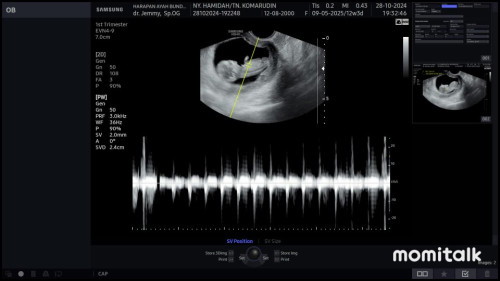

Kemarin USG Bun rahim ku tipis dan banyak pendarahan , trs diresepin obat penguat kandungan ππ₯Ή